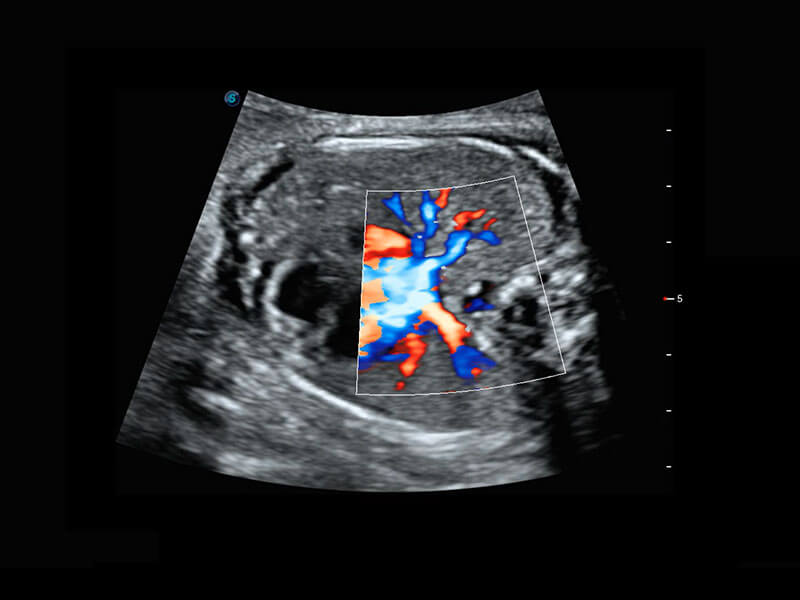

生殖健康

P60优异的图像质量搭载专科探头,在妇科基础疾病的诊断、卵泡生长的监测、输卵管通畅情况的判别等方面为您提供生殖应用方案。

• 腔内妇科-宫腔分离

• 腔内妇科-卵巢

• 腔内三维-宫内节育器

• 腔内三维-光影成像